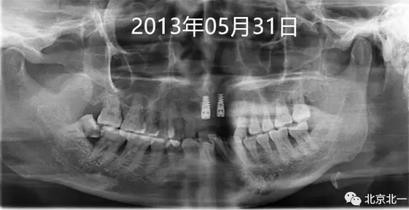

圖二:微創(chuàng)拔牙即刻種植當(dāng)天,采用ACTIVE 4.3*11.5,3.5*11.5(11 21位點(diǎn))

圖三:五月后二期手術(shù)